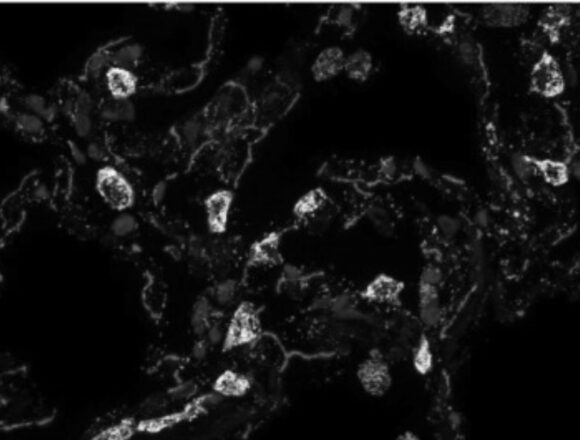

La Russia inizierà la sperimentazione umana del farmaco anti-cancro a metà 2025. Spariscono anche le metastasi. Sarà gratuito per tutti.

Alexander Gintsburg, direttore dell’Centro di Ricerca Nazionale Gamaleya, ha annunciato qualche settimana fa che la Russia inizierà a metà 2025...